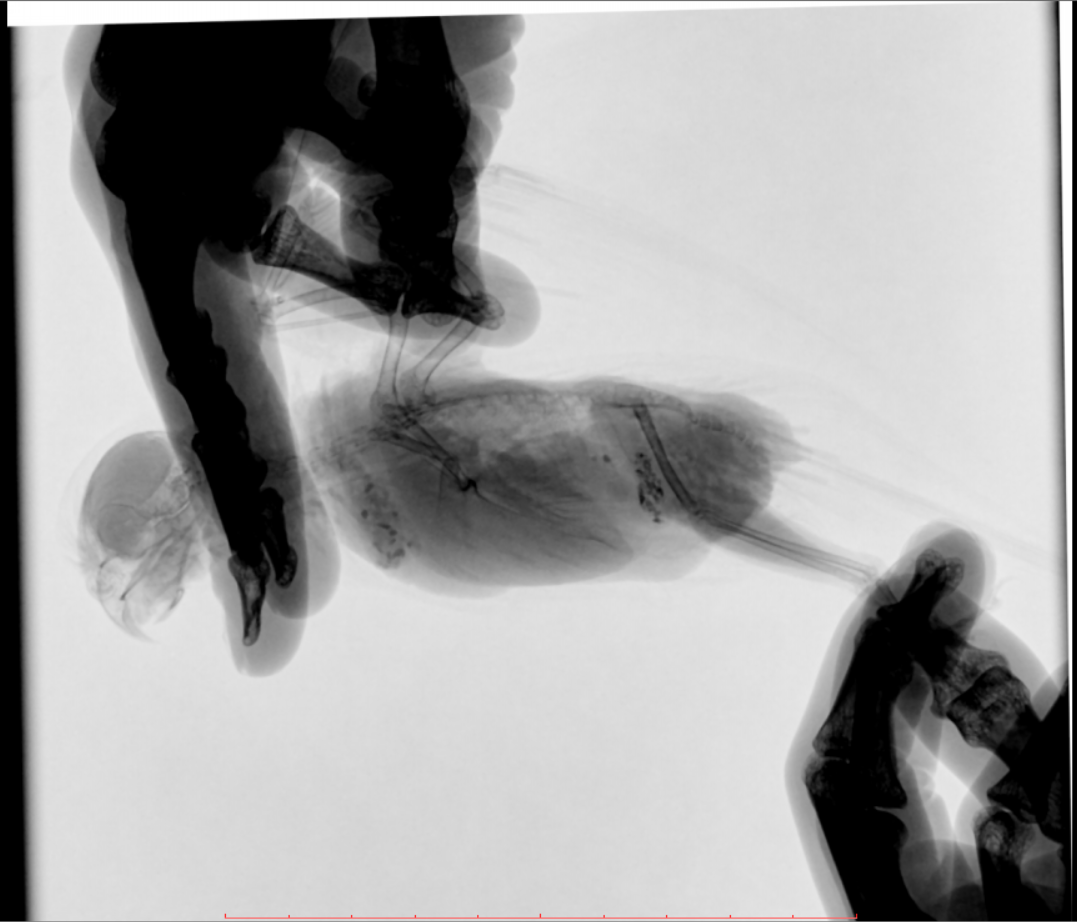

Во вторник отвозила птицу на рентген. Врач сказала, что очень сильно увеличена печень и другие органы. Также сдавлены воздухоносные мешки (из-за увеличенных внутренних органов). Отсюда - одышка. Также врач нашла перелом (старый?) ключицы. Попугая было очень сложно удерживать, поэтому снимки получились, возможно, недостаточно информативными - но какие уж получились((

@Zosia здравствуйте! Посмотрите, пожалуйста, снимки - видите ли вы на них отклонения, опухоли? Есть ли какие-то патологии? И одобряете ли вы назначенное лечение в нашей ситуации? Спасибо!

2.jpg

4.jpg

Печень видится мне увеличенной, но нужно чтобы @Zosia достоверно прочла снимки.

6.Тень семенников действительноу величена. Но снимок вами показан дурного качества. И бОльшего я сказать не могу.